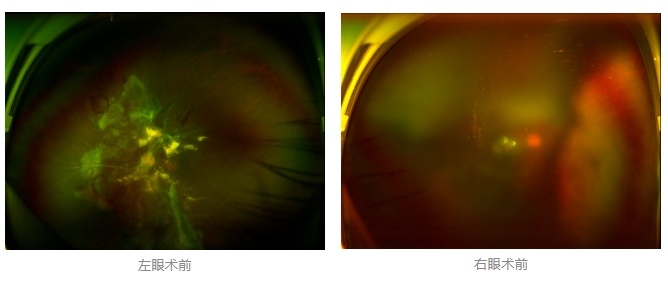

經(jīng)廈門眼科中心眼底病??菩姓魅瓮鯐圆z查后,確診其雙眼糖尿病視網(wǎng)膜病變VI期,伴發(fā)雙眼視網(wǎng)膜脫離和黃斑水腫,且右眼視網(wǎng)膜上增殖膜叢生,若再不盡快進行治療,恐有失明風險。

面對陳先生的復雜病情,王曉波主任采用玻璃體切割術聯(lián)合膜切除術等方式,精細剝離牽拉視網(wǎng)膜的增殖膜,復位脫離的視網(wǎng)膜,同時進行玻璃體腔注藥促進黃斑水腫吸收。

經(jīng)過規(guī)范化治療,術后2個月復查時陳先生的視力已有明顯改善,矯正視力從眼前指數(shù)提升至0.3,成功擺脫“失明危機”。但王曉波主任強調(diào):“這只是階段性勝利,后續(xù)治療不能松懈。”